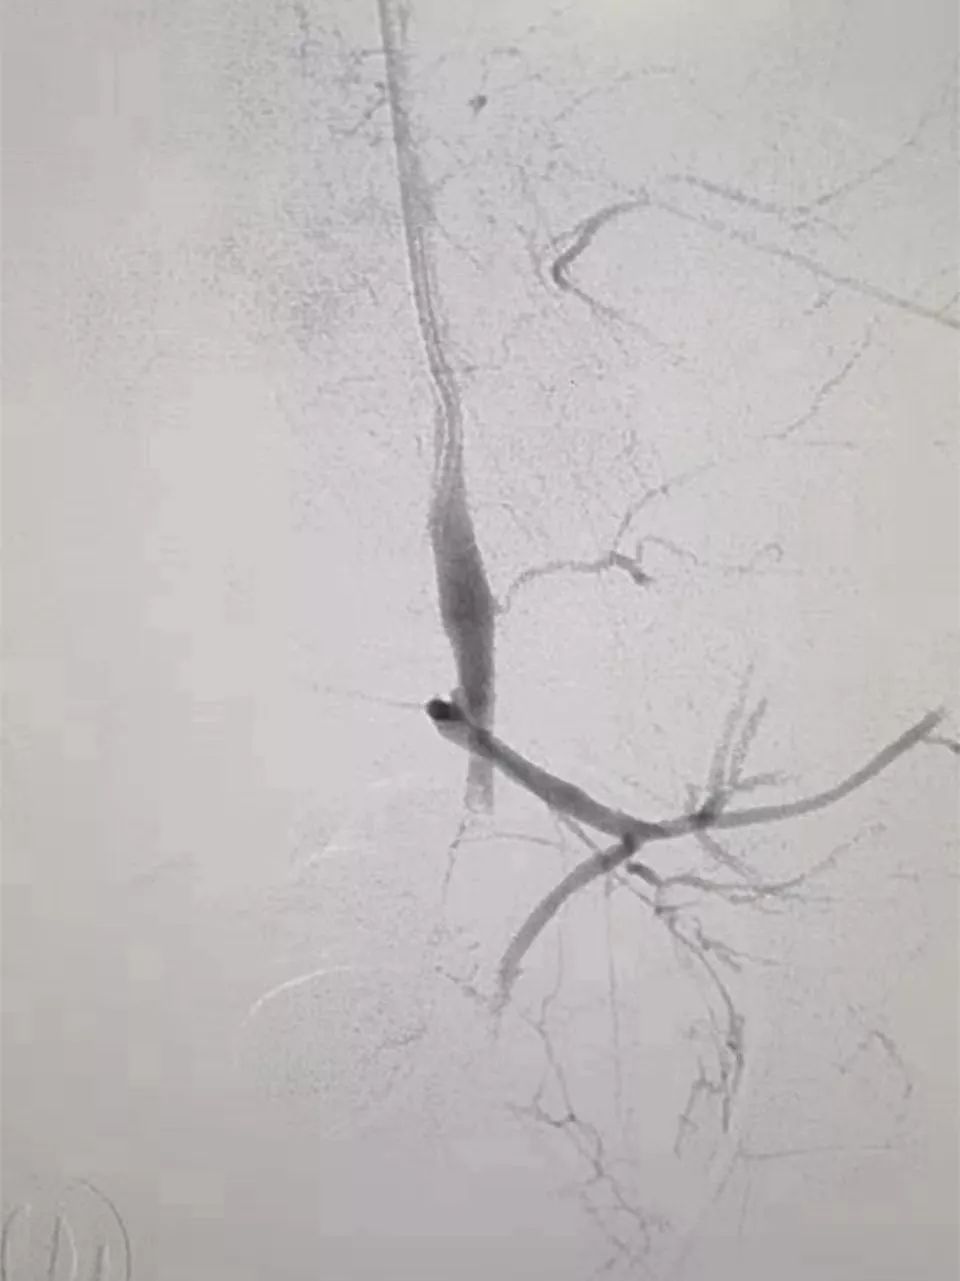

(栓塞前)

随后,医院立刻开通了抢救“绿色通道”!在各科室的通力配合下,介入中心纪斌医生在导管室行全麻下双侧子宫动脉造影术+栓塞术。通过导管鞘送入造影导管,导管尖分别置于双侧髂内动脉造影示双侧子宫动脉纤细、迂曲,周围分支增多、紊乱,左侧子宫动脉末梢见造影剂外溢及浓聚征象,遂超选择双侧子宫动脉成功后,透视下予以栓塞,造影复查患者双侧子宫动脉栓塞良好,血压回升至130/76mmHg,心率逐渐稳定,*体下**的出血停止了,已经扩大的瞳孔慢慢缩小,对光反射也逐渐恢复。妇产科医生去除手术钳后再次造影未见明显造影剂外溢征象,子宫出血停止。